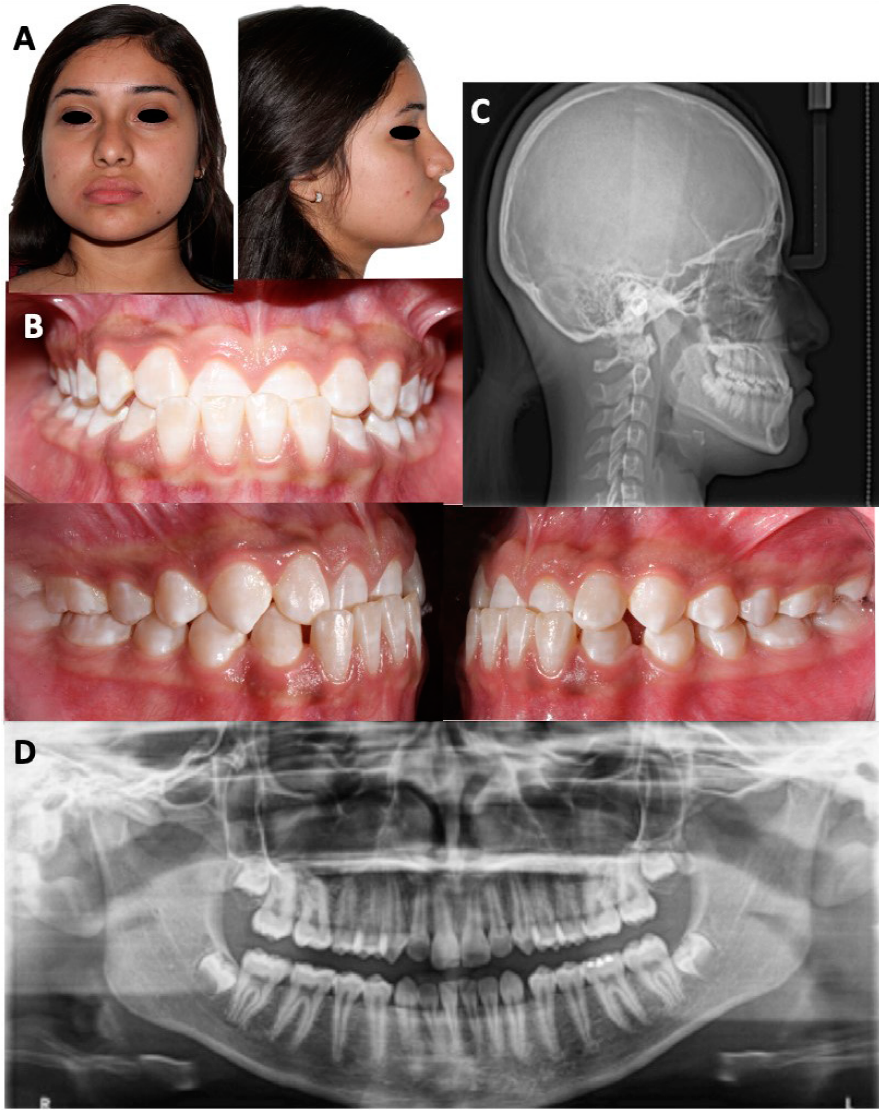

Paciente femenina de 13 años, sin antecedentes médicos relevantes, que acude con motivo de consulta “tengo mal mi mordida”. Facialmente, su tercio medio inferior estaba aumentado, cara redonda y perfil recto, nariz mediana y labios gruesos (Figura 1. A). Intraoralmente presentó dentición permanente, mordida cruzada anterior, maloclusión Clase I molar, Clase III canina izquierda con subdivisión, dientes medianos y cuadrados, mordida profunda, incisivos mandibulares protruidos e incisivos maxilares retruídos, línea media inferior desviada 1mm a la derecha, diastema entre los dientes 33 y 34 (Figura 1. B). Formas de arco cuadradas, sobremordida vertical de 4mm, sobremordida horizontal de -2mm, curva de Spee de 0mm, discrepancia de arco con exceso mandibular de 5.5mm.

Figura 1 Fotografías y radiografías iniciales. A. Fotografías extraorales iniciales; Tercio medio inferior aumentado, con perfil recto y cara redonda. B. Fotografías intraorales iniciales, mordida cruzada anterior, maloclusión Clase I molar, Clase III canina izquierda y Clase I derecha, dientes medianos y cuadrados, mordida profunda, incisivos mandibulares protruidos e incisivos maxilares retruidos. C. Radiografía lateral de cráneo; se observa la discrepancia esquelética, con un cuerpo mandibular largo; en el análisis de Lamparski se encuentra en un estadio 6 de desarrollo. D. Ortopantomografía; vía aérea permeable, rama mandibular izquierda más ancha, cóndilos asimétricos, presencia de 4 gérmenes de terceros molares.

En imagen radiográfica se observó vía aérea permeable, rama mandibular izquierda más ancha, cóndilos asimétricos, presencia de 4 gérmenes de terceros molares, relación de las raíces 2:1, niveles de crestas óseas sanas (Figura 1. C). En la radiografía lateral de cráneo, se observó la discrepancia esquelética, con un cuerpo mandibular largo; en el análisis de Lamparski se encuentra en un estadio 6 de desarrollo (Figura 1. D).